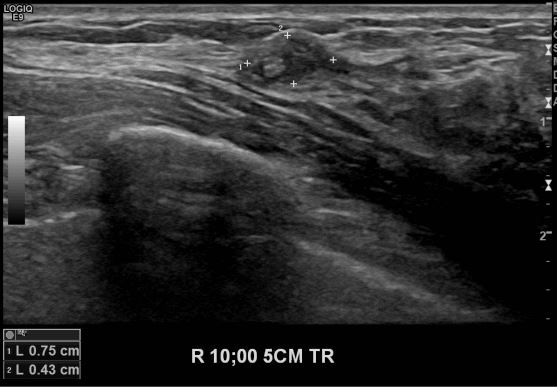

상기환자 유방의 멍울로 타원 경과관찰 권유받으신 분으로 본원 초음파상 좌측 10시 방향에서 5cm 떨어진 거리의 의심스러운 멍울 조직검사 시행하여 우측 침윤성 유관암 진단되었습니다.